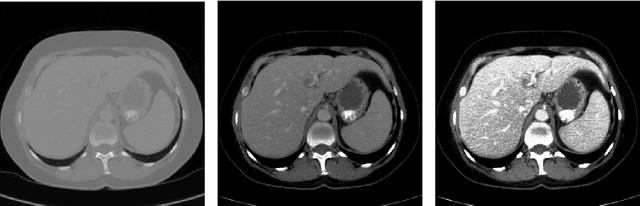

Abstract:Automatic segmentation of the liver and hepatic lesions is an important step towards deriving quantitative biomarkers for accurate clinical diagnosis and computer-aided decision support systems. This paper presents a method to automatically segment liver and lesions in CT and MRI abdomen images using cascaded fully convolutional neural networks (CFCNs) enabling the segmentation of a large-scale medical trial or quantitative image analysis. We train and cascade two FCNs for a combined segmentation of the liver and its lesions. In the first step, we train a FCN to segment the liver as ROI input for a second FCN. The second FCN solely segments lesions within the predicted liver ROIs of step 1. CFCN models were trained on an abdominal CT dataset comprising 100 hepatic tumor volumes. Validations on further datasets show that CFCN-based semantic liver and lesion segmentation achieves Dice scores over 94% for liver with computation times below 100s per volume. We further experimentally demonstrate the robustness of the proposed method on an 38 MRI liver tumor volumes and the public 3DIRCAD dataset.